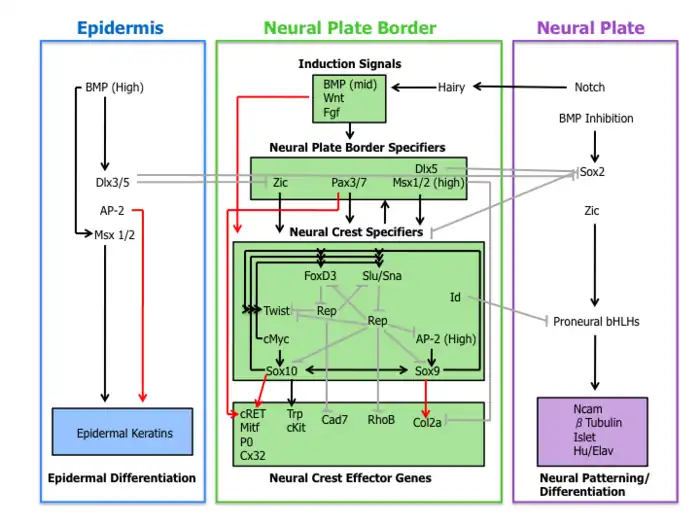

The syndrome is caused by mutations in any of several genes that affect the division and migration of neural crest cells during embryonic development (though some of the genes involved also affect the neural tube).[5] Neural crest cells are stem cells left over after the closing of the neural tube that go on to form diverse non-CNS cells in different parts of the body, including melanocytes, various bones and cartilage of the face and inner ear and the peripheral nerves of the intestines.[6] Type 1 is caused by a mutation in the PAX3 gene, while the gene that most often causes type 2 when mutated is MITF.[1][7] Type 3 is a more severe presentation of type 1 and is caused by a mutation in the same gene, while type 4 is most often caused by a mutation in SOX10.[2][8] Mutations in other genes can also cause the different types, and some of these have been given their own lettered subtypes. Most types are autosomal dominant.

The neural crest is a group of temporary migratory cells that are left over after the neural tube has closed (neurulation), around the fourth week of embryonic development. They are responsible for differentiating into a diverse group of cells that reach different areas of the body. The neural tube and neural crest are derived from the ectoderm; the neural tube goes on to form the brain and spinal cord, while the neural crest cells eventually go on to form various bones and cartilage of the skull and face by migrating through the pharyngeal arches. They also differentiate into the stria vascularis of the cochlea, the nerves and glia of the intestines (myenteric plexus), Schwann cells, which myelinate the peripheral nervous system to allow sufficient conductivity, odontoblasts, which produce dentin deep in the teeth, some neuroendocrine cells, connective tissue around the salivary, lacrimal, pituitary, thymus and thyroid glands, connective tissue of the eye, such as the stroma of the iris and cornea and the trabecular meshwork,[19] and melanocytes, including those in the stroma of the iris that give rise to brown eye colour through melanin. Neural crest cells also have a role in muscle formation, including the wall muscle of certain cardiac arteries.[6]

- Type 1 is caused by an autosomal dominant mutation in the gene PAX3.[1] PAX3, or paired box 3, is a transcription factor that has a role in maintaining an open window of time for certain neural crest cells (such as those of the head and eyes) to divide and migrate before their terminal differentiation (i.e. to maintain them in the stem-cell state). Mutations in this gene therefore prematurely arrest their division and migration, resulting in a minor lack of development of certain face cartilage and bones, as well as underdeveloped inner-ear structures and a lack of melanocytes in the iris stroma. Some evidence shows that PAX3 also regulates cells from before the neural crest forms, i.e. the neural tube, since mice with loss-of-function mutations in one of the copies of PAX3 have neural tube defects such as spina bifida or exencephaly.[5]

- Type 2A is caused by an autosomal dominant mutation in the gene MITF.[7] MITF, or microphthalmia-associated transcription factor, has a more specialised role in the neural crest and is more strictly involved after the neural crest forms (PAX3 and SOX10 have been found to activate MITF).[20] It is known to allow melanocytes, osteoclasts, mast cells and retinal pigment epithelial cells to divide and migrate. The involvement in osteoclasts explains why mutations in both copies of MITF can lead to bone hardening (osteopetrosis), as the osteoclasts are responsible for breaking down bone. MITF also activates transcription of tyrosinase, the enzyme that performs the first step in the creation of melanin (oxidising tyrosine). A mutation in a copy of MITF can also lead to Tietz syndrome, which is distinguished from Waardenburg syndrome by uniform albinism instead of patchy depigmentation.[5]

- Type 2E is caused by an autosomal dominant mutation in the gene SOX10.[4]